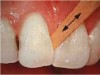

A carious lesion develops in three stages of demineralization. The first stage in demineralization of enamel is called the incipient lesion or “white spot” (Figure 1). This beginning carious lesion can be reversed with the daily use of fluoride or calcium and phosphate, persistent oral hygiene care, and a reduction of refined carbohydrates. The second stage involves the progression of demineralization leading to the DEJ and into the dentinal layer. The third stage is the actual cavitation in the dentinal layer. Neither of the last two stages can be reversed and require mechanical removal of dental caries.

Figure 1. Incipient caries.

Figure 1